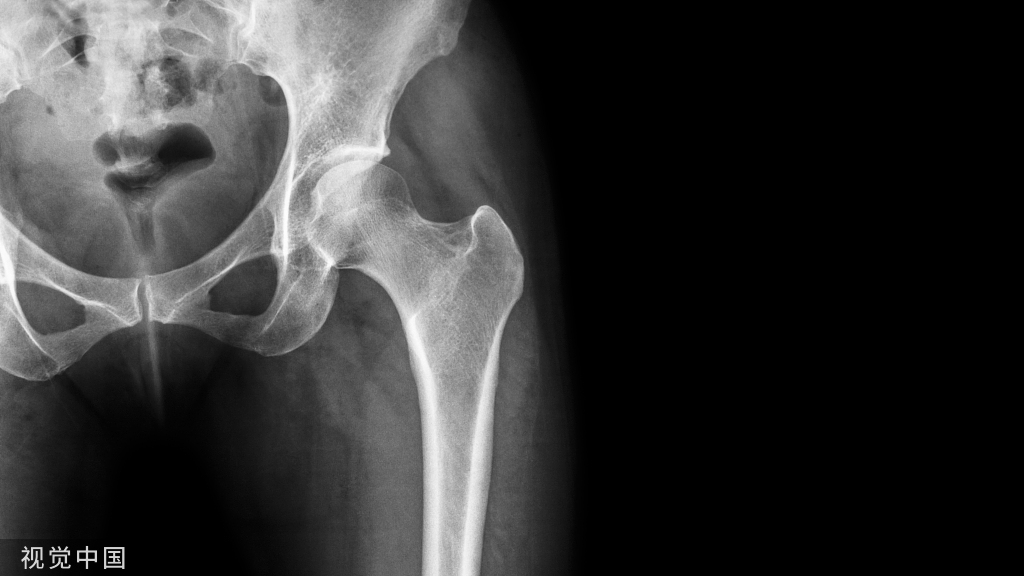

图1:30岁男性,予以关节镜下Endobutton固定,术前及术后片。